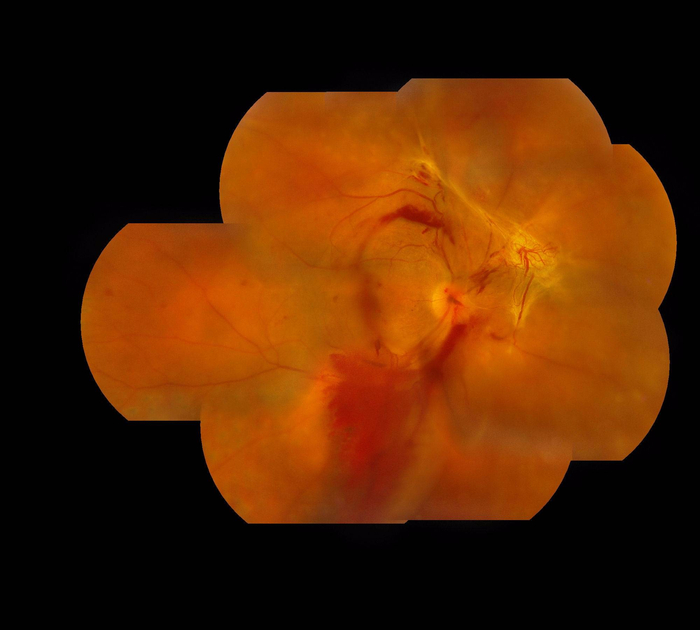

图1:显示增殖性糖尿视网膜病变导致的玻璃体移位出血以及牵引性视网膜脱落

深圳希玛林顺潮眼科医院院长、国际名医林顺潮介绍,糖尿病引发的视网膜病变并未得到重视。糖尿病视网膜病变初期通常都是无声无息、没有明显病征。如果一旦出现视力模糊等症状时,应立刻求医及早接受合适治疗。林顺潮举例,曾接诊过一名40岁的患者,患高血压、糖尿病6年多,因视力下降前来就诊,被诊断为“双眼糖尿病性视网膜病变”,当时建议应及时采取双眼激光治疗,但患者并未采纳医生建议。一年后视力持续变差前来就诊,此时双眼晶体混浊、右眼视力0.1,左眼视力仅可看见手指数,经过详细的检查,此时已病变严重,出现牵拉性视网膜脱离和玻璃体积血、黄斑囊样水肿等多发病变。